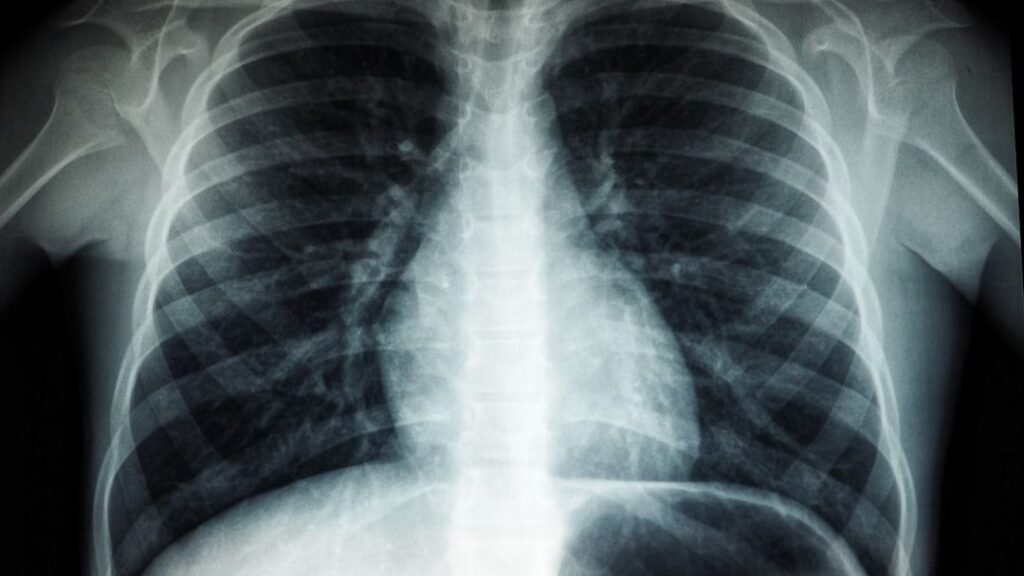

4. X-Rays: A Glowing Screen No One Expected

In 1895, physicist Wilhelm Röntgen was experimenting with cathode rays in a darkened lab, playing with vacuum tubes the way some people tinker with old radios today. He noticed that a nearby fluorescent screen, which shouldn’t have reacted at all, started glowing from an invisible kind of radiation. He became obsessed with figuring out what was happening, eventually discovering that this new type of ray could pass through soft tissue but not bone or metal, revealing hidden structures inside the body.

Within months, doctors were using X-rays to look at broken bones and foreign objects inside patients, a radical shift from relying only on touch, guesswork, and surgery. Medical diagnosis changed forever, and imaging technology kept evolving into CT scans, mammograms, and more advanced systems we use today. All of that traces back to a strange glow in a dark room, which could easily have been dismissed as a faulty setup. Instead, Röntgen dug in, and his curiosity opened an entire new way of seeing inside the human body without cutting it open.